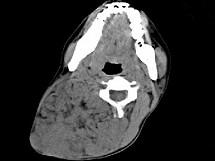

问题 女,32岁,颈部包块8年余,包块逐渐长大,CT如图所示,最可能的诊断为 ( )

选项 A、颈部神经鞘瘤 B、颈部异位甲状腺 C、颈部横纹肌肉瘤 D、颈部巨大血管瘤 E、颈部神经纤维瘤

答案 D